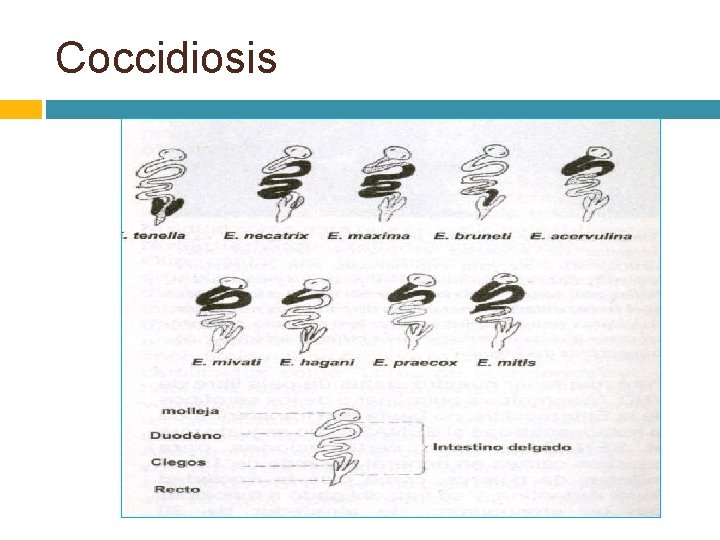

Coccidiosis Eimeriosos

Coccidiosis